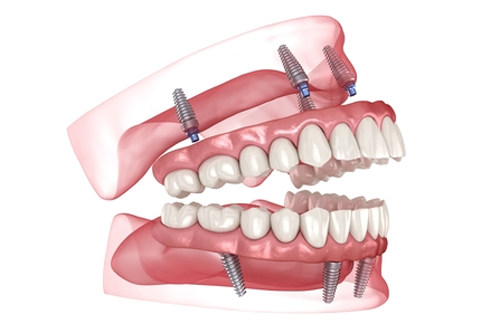

半口种植牙:2万元起

全口种植牙:5万元起

沈阳国民口腔医院汇聚了一批经验充足的口腔医师,每位医生都经过严格筛选和特色培训。我们的种植牙医生拥有数千例成功实例,熟练掌握各种复杂种植技术,包括即刻种植、小创口种植、All-on-4/6等较高技术。矫正医生精通各类矫治技术,能够为不同年龄段的患者制定个性化矫正方案。